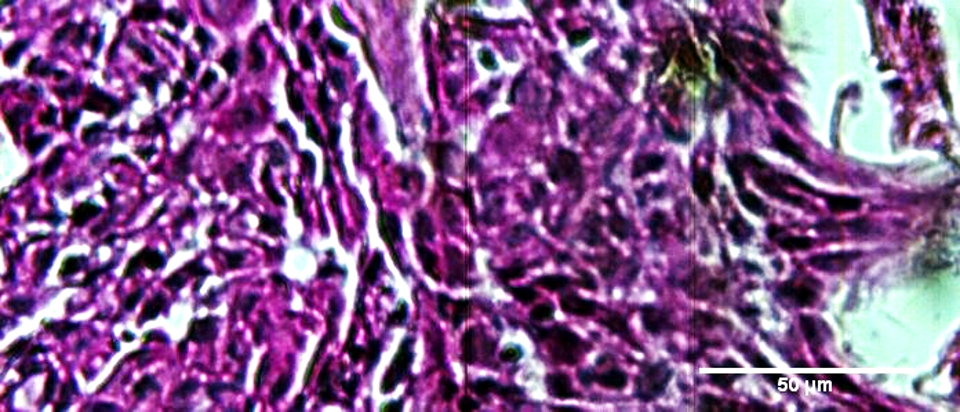

Spectral identification of cancerous tissue based on its stain free endogenous optical properties

Hyperspectral Microscopy produces high resolution visible near infrared (VNIR) optical spectral data in each submicron pixel of an image. This data-rich imaging technology is transforming digital pathology in areas ranging from cancer and Alzheimer's diagnosis to stem cell characterization.